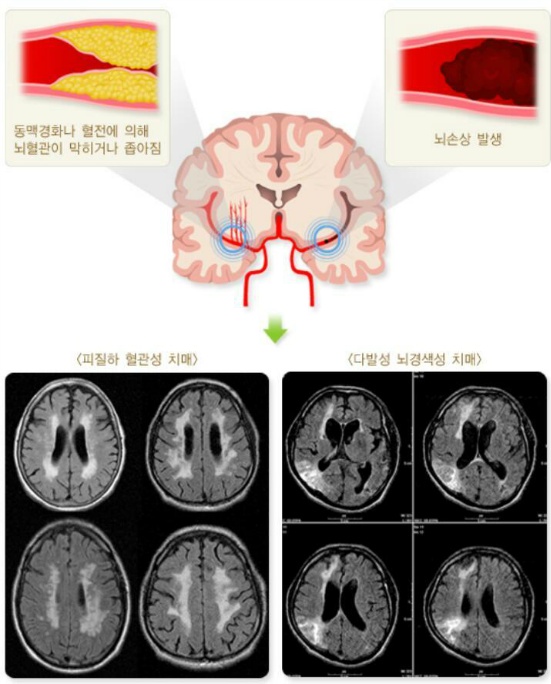

알츠하이머"치매"